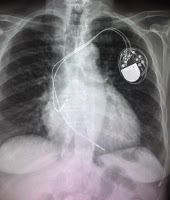

Unicamerales: como su nombre lo indica colocan un catéter (cable) en una cámara del corazón (ventrículo derecho). Se reservan para los pacientes con fibrilación auricular crónica y pacientes menores de 75 años de edad, donde el riesgo de colocar otro cable es mayor.

Mediante una técnica de punción se realiza el acceso al sistema venoso y la colocación del catéter empleando los rayos X. Se realiza la fijación del marcapasos al músculo y se cierran los planos musculares hasta el cierre de la piel.

Se realiza en un área de cuidados coronarios y requiere la observación continua del ritmo cardíaco y control con radiografía de tórax.

El primer control debe de realizarse a los 15 días con una radiografía de tórax y un electrocardiograma . El